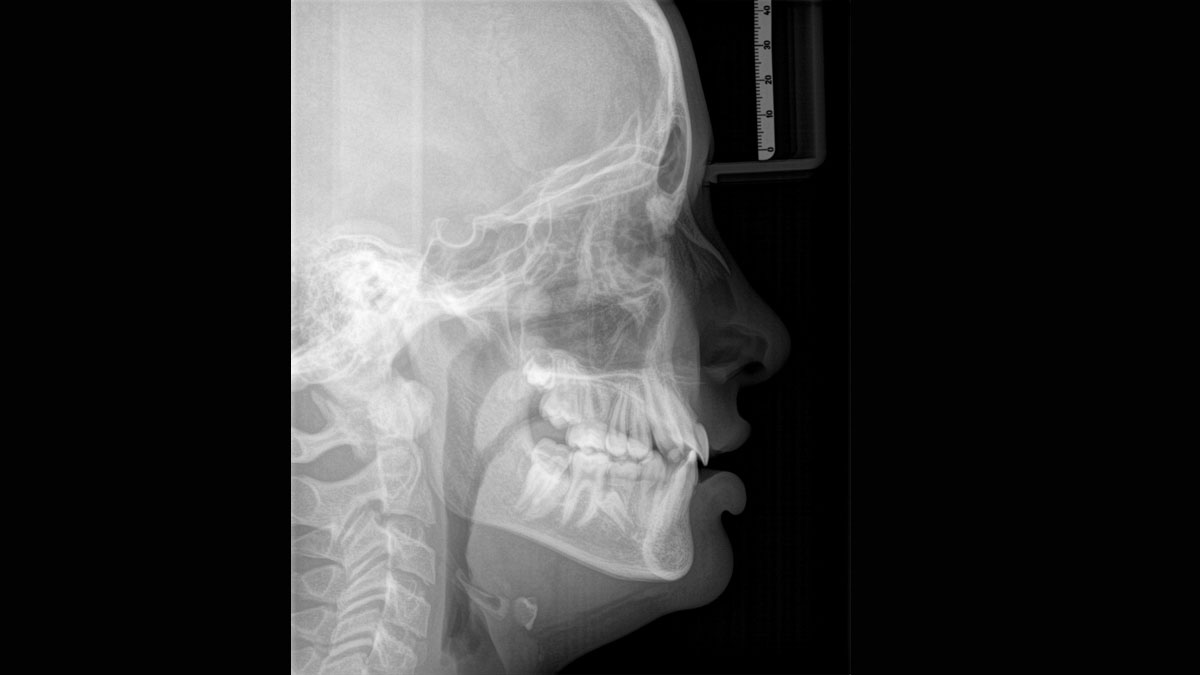

Het hoogwaardige 2D/3D-röntgenapparaat met uitgebreide mogelijkheden voor elke praktijk. Of het nu gaat om een puur 2D-apparaat of een 3D-module, de Orthophos S is een betrouwbare partner die helemaal is geoptimaliseerd voor dagelijkse taken. De CsI Plus-sensor met autofocusfunctie geeft heldere beelden, zelfs in anatomisch moeilijke gevallen. De automatische patiëntpositionering in combinatie met het gepatenteerde occlusale bijtblok maakt een eenvoudige en tijdbesparende patiëntpositionering mogelijk. Voor gebruik in orthodontie is de Orthophos S ook verkrijgbaar met een optionele ceph-arm. Uw praktijk toekomstbestendig houden is voor ons belangrijk en daarom kan de cephalometrische arm op elk moment achteraf worden ingebouwd.

Met gemotoriseerde schedel- en voorhoofdondersteuning, automatische meting van de schedelbreedte, laser lichtlijnen en geïntegreerde handvatten voor extra stabiliteit.